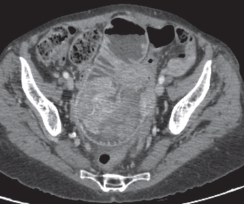

LUIS CESAR HERNANDEZ MORENO, ALEJANDRO JAVIER KOTLIK AGUILERA, JUAN RAMÓN BOMBIN FRANCO, JAIME ARTURO RECASENS THOMAS

|